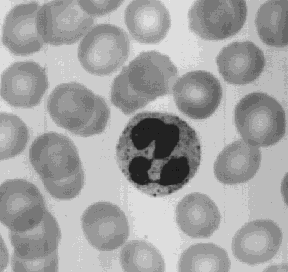

The most abundant of the WBCs. This photomicrograph shows a single neutrophil surrounded by red blood cells.

Neutrophils squeeze through the capillary walls and into infected tissue where they kill the invaders (e.g., bacteria) and then engulf the remnants by phagocytosis.